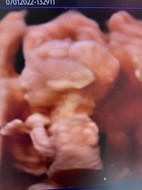

สาวน้อยของแม่ 21 week แล้วค่ะ